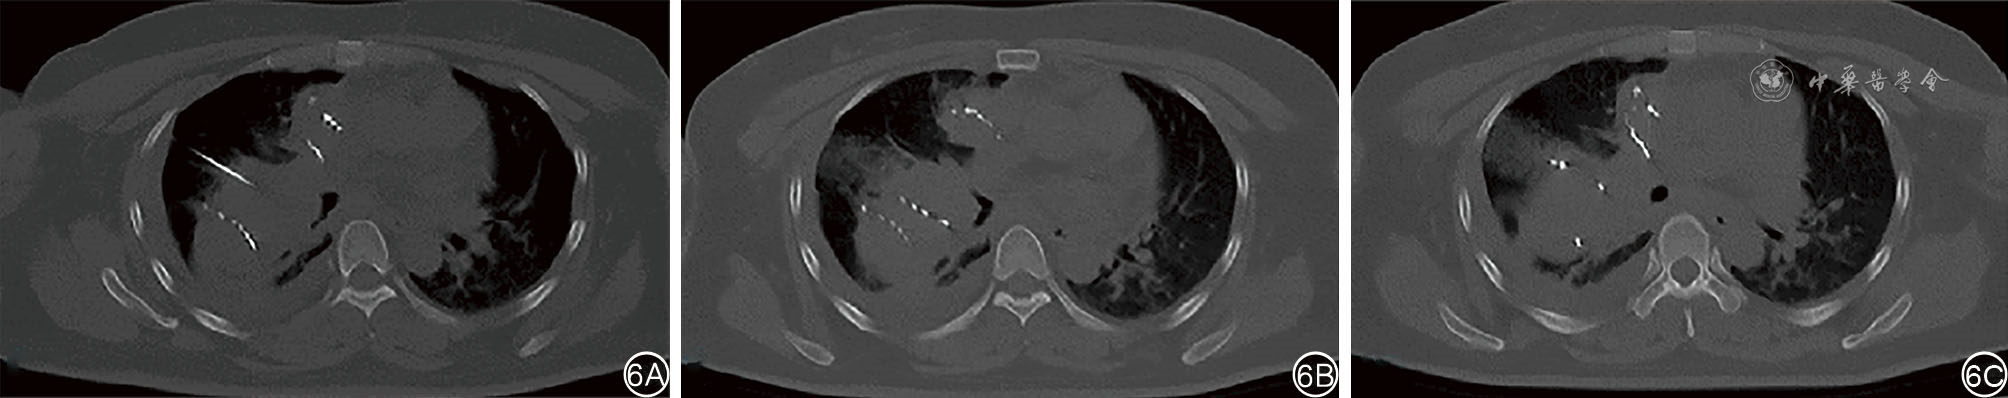

We present a case of a 40-year-old female patient with midline carcinoma, who was admitted for chest pain and cough and diagnosed with concurrent mediastinal and pulmonary metastases. Single-agent chemotherapy proved ineffective and her clinical symptoms aggravated, accompanied by tracheal and superior vena cava compression. Following multidisciplinary consultation, CT-guided 125Ⅰ seed implantation was initially performed. Local tumors regressed postoperatively while partial pulmonary metastatic lesions progressed, prompting seed reimplantation combined with bronchial arterial chemoembolization, followed by concurrent anlotinib targeted therapy and sintilimab immunotherapy. After six months of comprehensive treatment, the thoracic tumors resolved, lymph nodes shrank, radiological evaluation indicated partial response, and the patient's clinical symptoms were significantly relieved. This case demonstrates that the integrated regimen of interventional local therapy plus targeted and immunotherapy offers a viable therapeutic approach for inoperable midline carcinoma patients with refractory conventional chemotherapy, enabling rapid symptom relief and improved treatment efficacy.